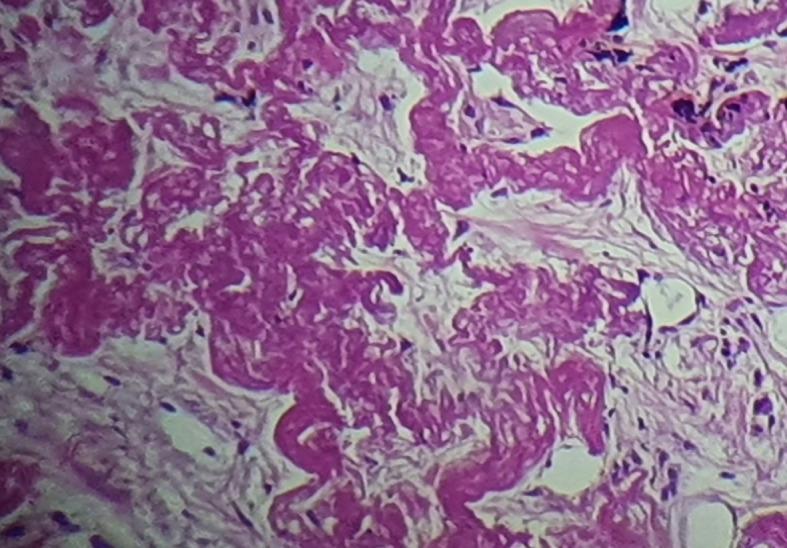

Idiopathic pleuroparenchymal fibroelastosis (IPPFE) is a very rare and a slowly conspicuous progressing chronic lung disease, which usually involves the upper lobes of the lung. This unusual disease, first recognized as a rare idiopathic interstitial pneumonia in 2013, is characterized by dense fibrosis of the visceral pleura and the subjacent lung parenchyma accompanied by elastosis predominating in the subpleural alveolar walls. In the interest of improving our understanding of this uncommon disease, we report a case of IPPFE established by pathology results. A 73-year-old male patient, smoker, with a medical history of chronic obstructive pulmonary disease, presented since January 2022 with a gradual worsening of dyspnea on exertion and productive cough with weight loss. The chest X-ray detected a thoracic distention. The chest high resolution computed tomography revealed biapical subpleural parenchymatous condensations with tractive bronchiectasis and pleural retraction in the right upper lobe and diffuse bilateral cento-lobular emphysema. A scan-guided trans-parietal lung biopsy showed lung parenchyma tattooed with anthracosic deposits, largely remodeled by fibrous tissue, intermingled with numerous wavy and refractive dyselastotic structures in polarized light. The orcein staining confirmed the presence of excess elastosic fibers within these lesions. All etiological investigations were negative. His lung function studies revealed a reversible obstructive ventilatory disorder. Following a multidisciplinary discussion, the diagnosis of IPPFE was confirmed on the basis of the distribution in the upper lungs on chest computed tomography combined with pathology pattern. This case emphasizes the atypical misleading radiological presentation of IPPFE and the key role of pathological results in establishing the diagnosis. Hence, further studies are needed to improve our understanding of this uncommon disease and to establish clear-cut guidelines for IPPFE diagnosis and management.

特发性胸膜肺弹力纤维增生症(IPPFE)是一种非常罕见且进展缓慢的慢性肺部疾病,通常累及肺部上叶。这种不常见的疾病于 2013 年首次被认为是一种罕见的特发性间质性肺炎,其特征为脏层胸膜和下肺部实质的致密纤维化,伴弹性组织增生为主的亚胸膜肺泡壁。为了提高对这种罕见疾病的认识,我们报告了一例经病理证实的 IPPFE 病例。一名 73 岁男性患者,吸烟者,有慢性阻塞性肺疾病病史,自 2022 年 1 月以来,逐渐出现劳力性呼吸困难加重和咳痰伴体重减轻。胸部 X 线检查发现胸部膨胀。胸部高分辨率计算机断层扫描显示右上叶双肺尖下胸膜实质混浊,伴有牵引性支气管扩张和胸膜回缩,以及双侧弥漫性中心小叶性肺气肿。经皮肺活检显示肺实质有炭末沉着,大部分被纤维组织重塑,在偏光下可见许多波浪状和折射性弹性不良结构。奥辛染色证实这些病变中存在过多的弹性纤维。所有病因学调查均为阴性。他的肺功能研究显示存在可复性阻塞性通气障碍。经过多学科讨论,根据胸部 CT 检查中肺部上叶的分布和病理模式,确诊为 IPPFE。 该病例强调了 IPPFE 不典型的误导性放射学表现以及病理结果在确立诊断中的关键作用。因此,需要进一步研究以提高对这种罕见疾病的认识,并为 IPPFE 的诊断和管理制定明确的指南。